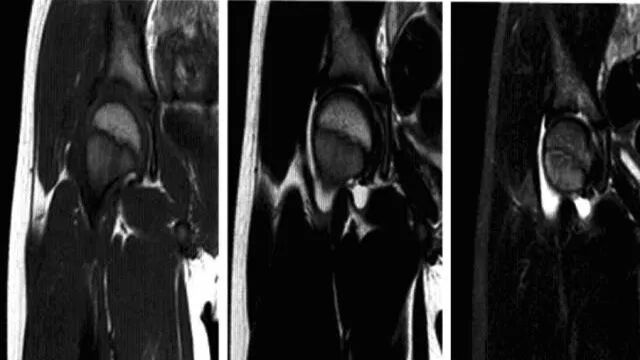

髋关节一过性骨质疏松

又称髋关节暂时性骨质疏松、暂时性骨髓水肿综合征,是一种病因不明、发病率低的自限性疾病。临床以无外伤史的疼痛为特征并在6-12个月内完全好转为其诊断标准。

病理:骨髓脂肪坏死、骨吸收、骨髓组织周围水肿样变化和轻度纤维化,常伴血管性充血或间质性出血,以及滑膜炎表现,有时可见软骨下骨折,伴有骨痂和肉芽组织,但无骨坏死表现。

临床表现:好发于中年男性或怀孕3个月左右女性,单侧或双侧均可发病,主要症状为无任何诱因出现髋部剧烈疼痛,呈渐进性并放射至膝关节,伴髋关节活动不利、跛行,疼痛加重约在发病后4-8周,并持续一段时间,之后疼痛逐渐减轻至消失,病程约6-12个月,髋部肌肉及股四头肌呈失用性萎缩。实验室检查阴性。

影像诊断:平片及MRI是本病主要诊断手段。

1、平片:活动期表现骨质疏松,股骨头和转子间弥漫性骨密度减低,股骨头软骨下骨皮质吸收,髋臼受累程度轻,无骨侵蚀或破坏,关节间隙保持正常。

2、MRI:骨头至转子间在T1WI低信号,T2WI及脂肪抑制呈均匀一致高信号,无局灶性改变,多伴髋关节积液,周围肌肉层次清晰,随访多于6-10个月内恢复正常,无后遗症。